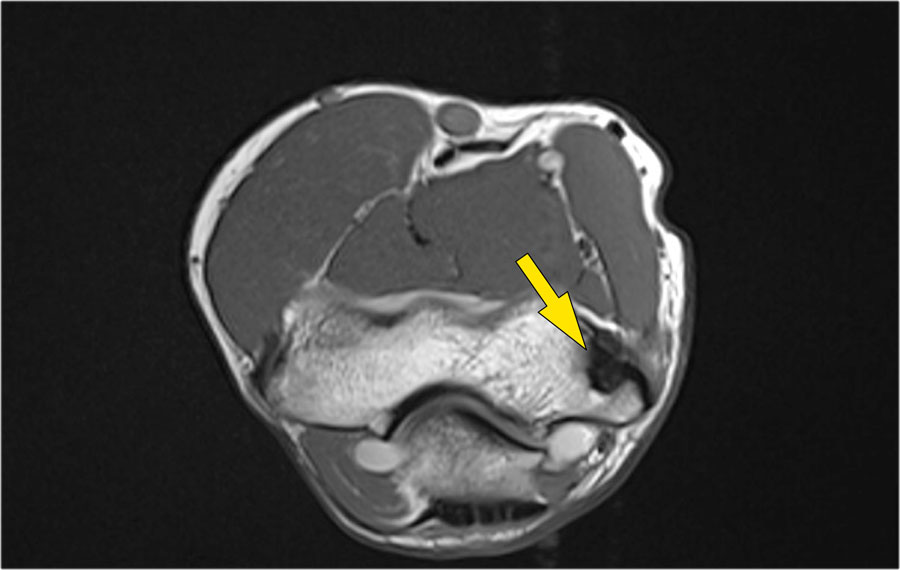

Những hình ảnh này của một nam giới 23 tuổi bị ngã chống tay khi đang trượt ván hai tuần trước.

Khi khám lâm sàng, ghi nhận giảm biên độ vận động khớp khuỷu và đau khi ấn dọc theo mặt ngoài.

Cấu trúc nào nằm phía sau chỏm quay trên hình ảnh cắt ngang?

Cấu trúc phía sau chỏm quay là dây chằng vòng.

Nó không đều và dày lên do hậu quả của trật khớp ra sau.